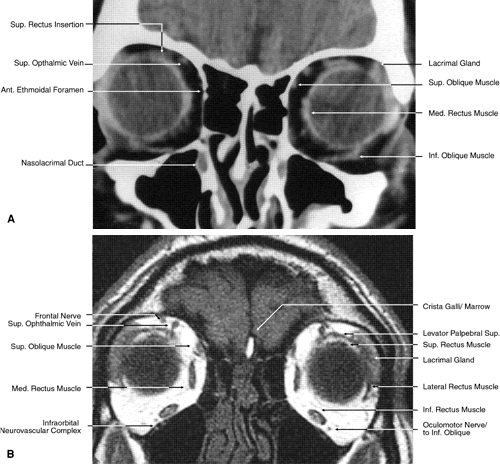

The globe is shown in Figure 12. The orbit and periorbital structures are shown in Figures 13 through 16, and the optic canal is shown in Figures 17 through 26. The cavernous sinus and optic chiasm are shown in Figures 27 and 28, and the posterior visual pathway and cranial nerves are shown in Figures 29 through 33.

Fig. 17. Coronal images through anterior orbit. A. Computed tomography scan. B. T1-weighted magnetic resonance imaging.

Fig. 18. Coronal images through midglobe. A. Computed tomography scan. B. T1-weighted magnetic resonance imaging.

Fig. 19. Coronal images through midorbit posterior to the globe. A. Computed tomography scan.B. T1-weighted magnetic resonance imaging.

Fig. 20. Coronal images through orbital apex. A. Computed tomography scan. B. T1-weighted magnetic resonance imaging. C. Anatomic section of a cadaver head at the level of the orbital apex.